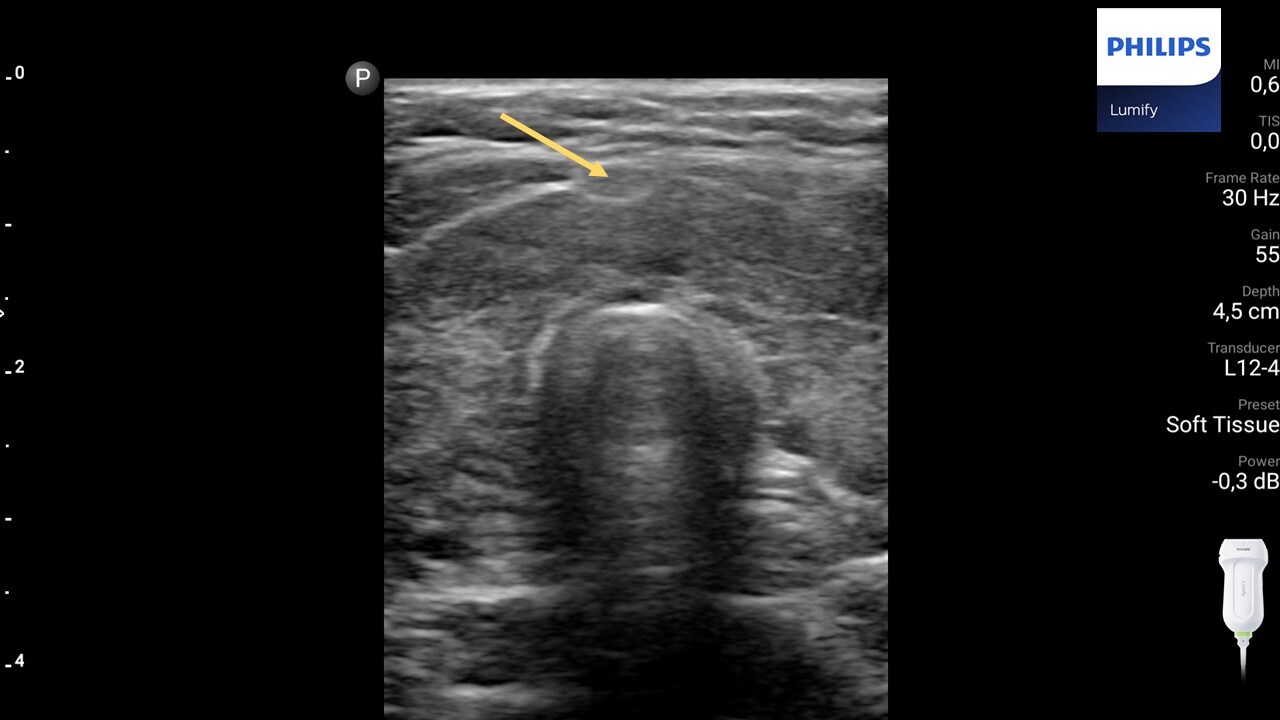

Węzeł chłonny (strzałka) widoczny przy cieśni tarczycy. Głowica liniowa Philips Lumify.

4. U pacjentów z chorobą Hashimoto charakterystyczna jest obecność węzłów chłonnych przedtchawiczych, widocznych poniżej biegunów dolnych tarczycy i przy jej cieśni. Węzły te zdecydowanie rzadziej obserwuje się u pacjentów z chorobą Gravesa-Basedowa.